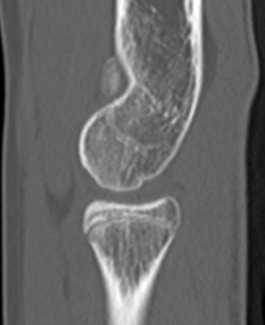

Elbow OAElbow OA sagittal CT

Elbow osteoarthritis and & stiffness  www.boneschool.com/elbow-OA